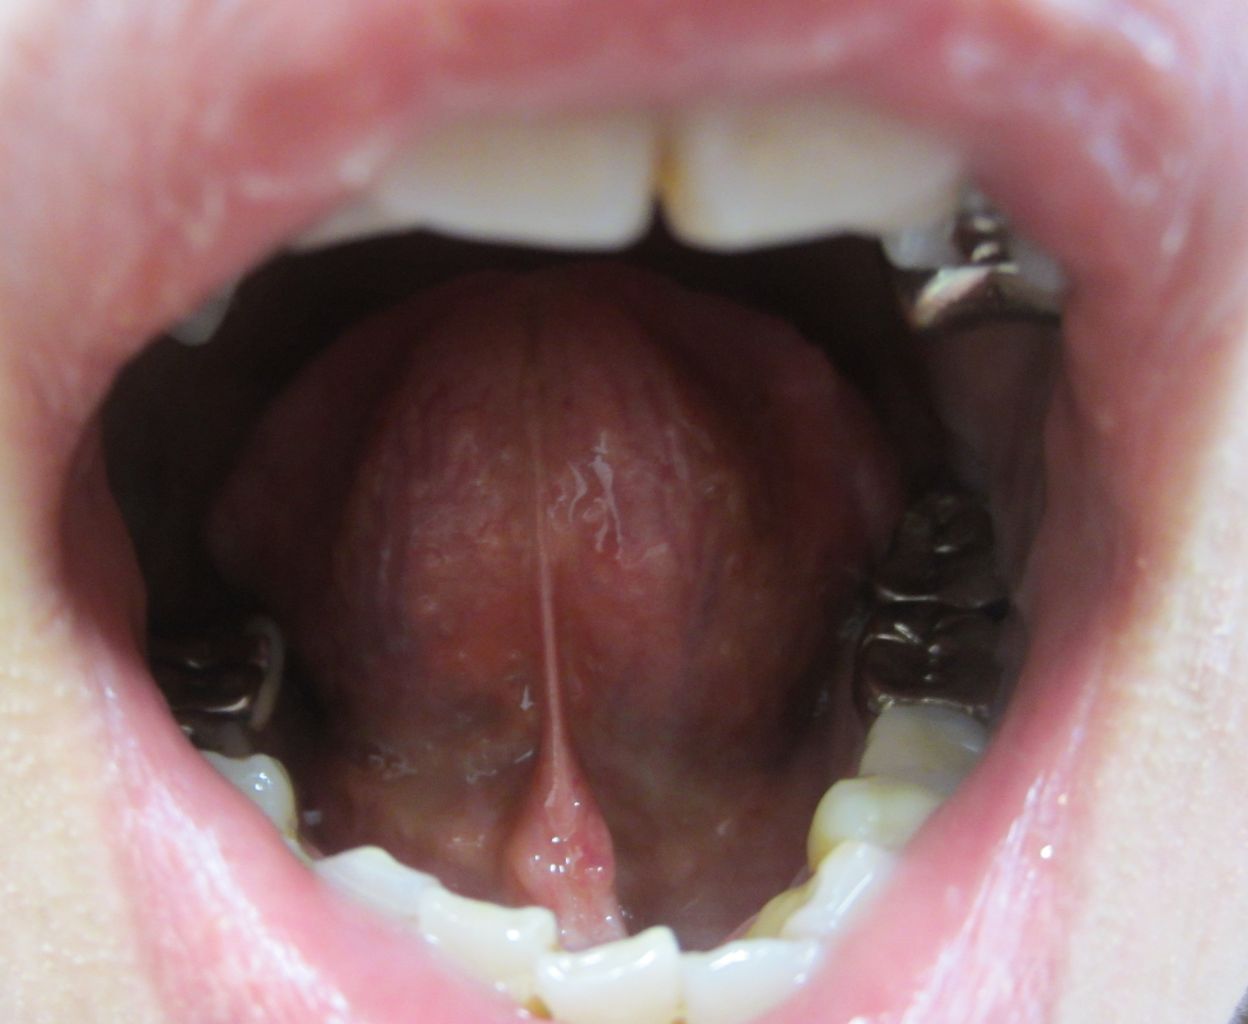

¡Ú2014ǯ1·î8Æü´ÁÊýÌôÉþÍÑ84Æü¸å¤ÎÀå¤Îɽ¡Û

¡Ú2014ǯ1·î8Æü´ÁÊýÌôÉþÍÑ84Æü¸å¤ÎÀå¤Î΢¡Û